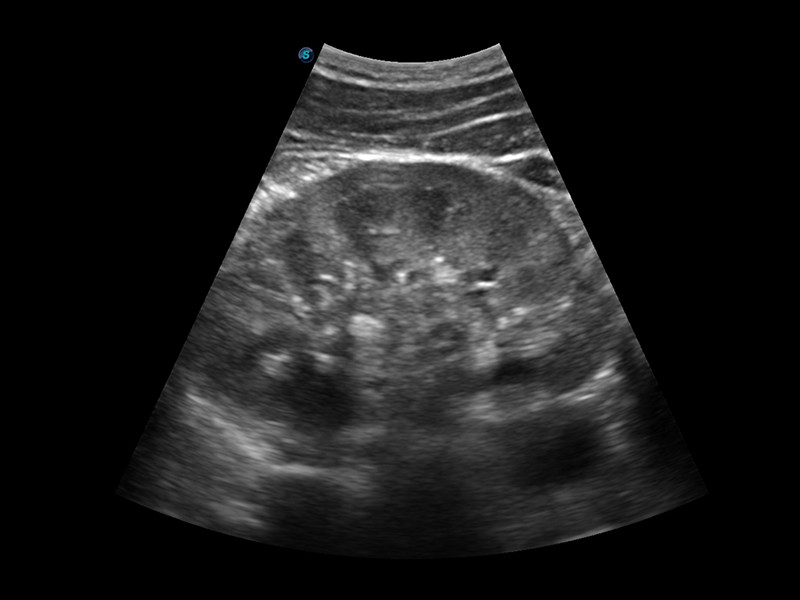

Sonda Convexa 3C-A

Ideal para diversas aplicações, como abdômen, ginecologia, obstetrícia, urologia

e até biópsia de abdômen.